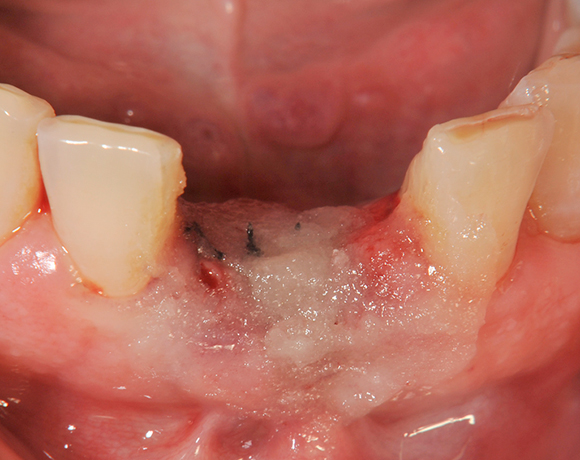

Die Keramikimplantate der Fa. Dentalpoint lassen sich auch zur Sofortimplantation verwenden. Das bedeutet, dass nach Extraktion nicht beherdeter Zähne direkt die Implantate gesetzt werden können.

Im vorliegenden Patientenfall wurden die beiden nicht erhaltungswürdigen, mittleren Unterkieferschneidezähne durch zwei Vollkeramikimlpantate ersetzt.